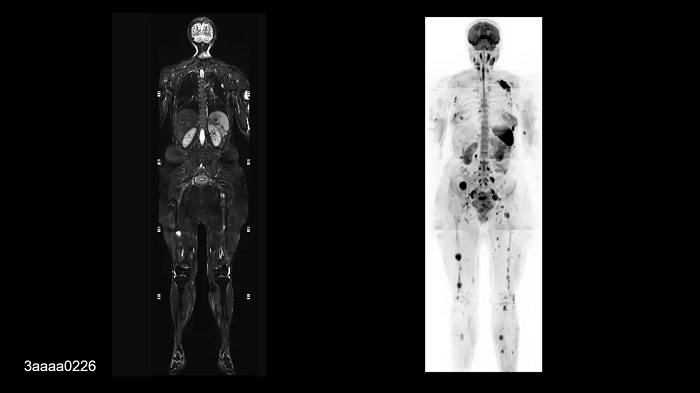

Whole-body imaging

Full Whole-Body Coverage in Only 5 Stations

Enhanced whole-body DWI quality due to BioMatrix SliceAdjust.

- BioMatrix Head/Neck 20

- BioMatrix Spine 72

- 2× Body 18

- Peripheral Angio 36

Image Credit: University Hospital Tubingen, Germany